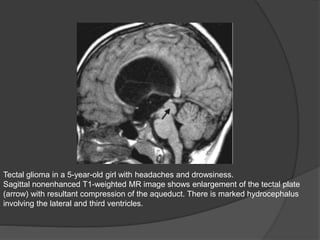

Tectal glioma in a 5-year-old girl with headaches and drowsiness.

Sagittal nonenhanced T1-weighted MR image shows enlargement of the tectal plate

(arrow) with resultant compression of the aqueduct. There is marked hydrocephalus

involving the lateral and third ventricles.